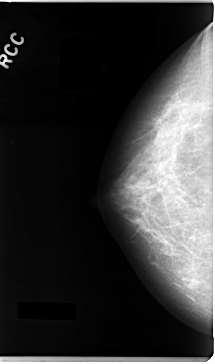

C_0026_1.RIGHT_MLO

RIGHT_CC LINES 4720 PIXELS_PER_LINE 2784 BITS_PER_PIXEL 12 RESOLUTION 50 NON_OVERLAY

RIGHT_MLO LINES 4696 PIXELS_PER_LINE 2776 BITS_PER_PIXEL 12 RESOLUTION 50 NON_OVERLAY